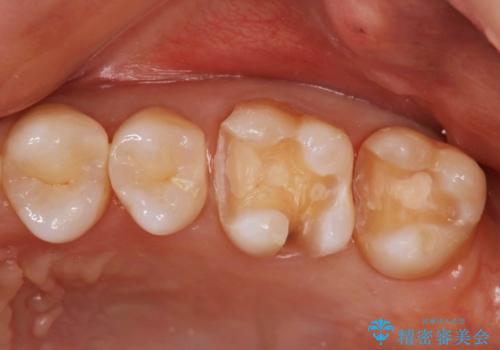

- 矯正しモチベーションが高くこの際メタルフリーにしたいという主訴で来られた患者様です。

検査してみたところ、後ろの歯も虫歯があったので治療させていただくことになりました。

左上奥歯2本治療することになりました。

e-max インレー 1本 77000円(税込)

- 154,000円費用は治療当時の料金となります